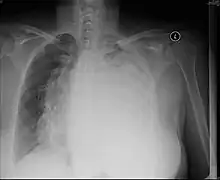

A pleural effusion is an accumulation of fluid inside the pleural space. If this collection of fluid gets large enough, it can also push structures in the chest away from it and cause a mediastinal shift. However, a pleural effusion can also pull mediastinal structure towards itself. If this is the case, then there is an underlying condition causing collapse of the lung on that side. An example is a tumor obstructing a bronchus and causing lung collapse and pleural effusion.[3]